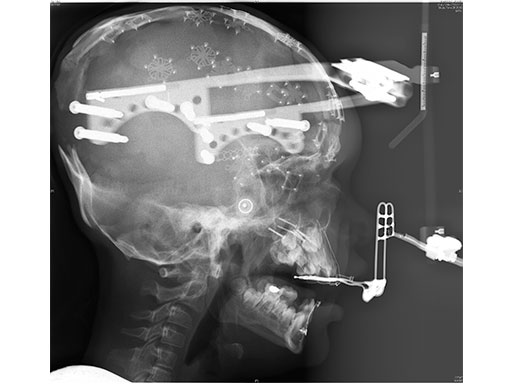

An 8-year-old girl with Apert Syndrome (Fig 5) was examined after being treated at another institution. The cause for loss of cranial bone was unknown. An anterior and posterior cranial expansion was given to treat the increased intracranial pressure.

After that healed, a simultaneous PSI cranioplasty and Le fort II osteotomy with zygoma repositioning were performed. The PEEK implants were fixated using MatrixNeuro ULP implants (Fig 6). A midface distraction device was then mounted on the PSI implants and distracted the Lefort 2 segment to treat the patient's sleep apnea (Fig 7).